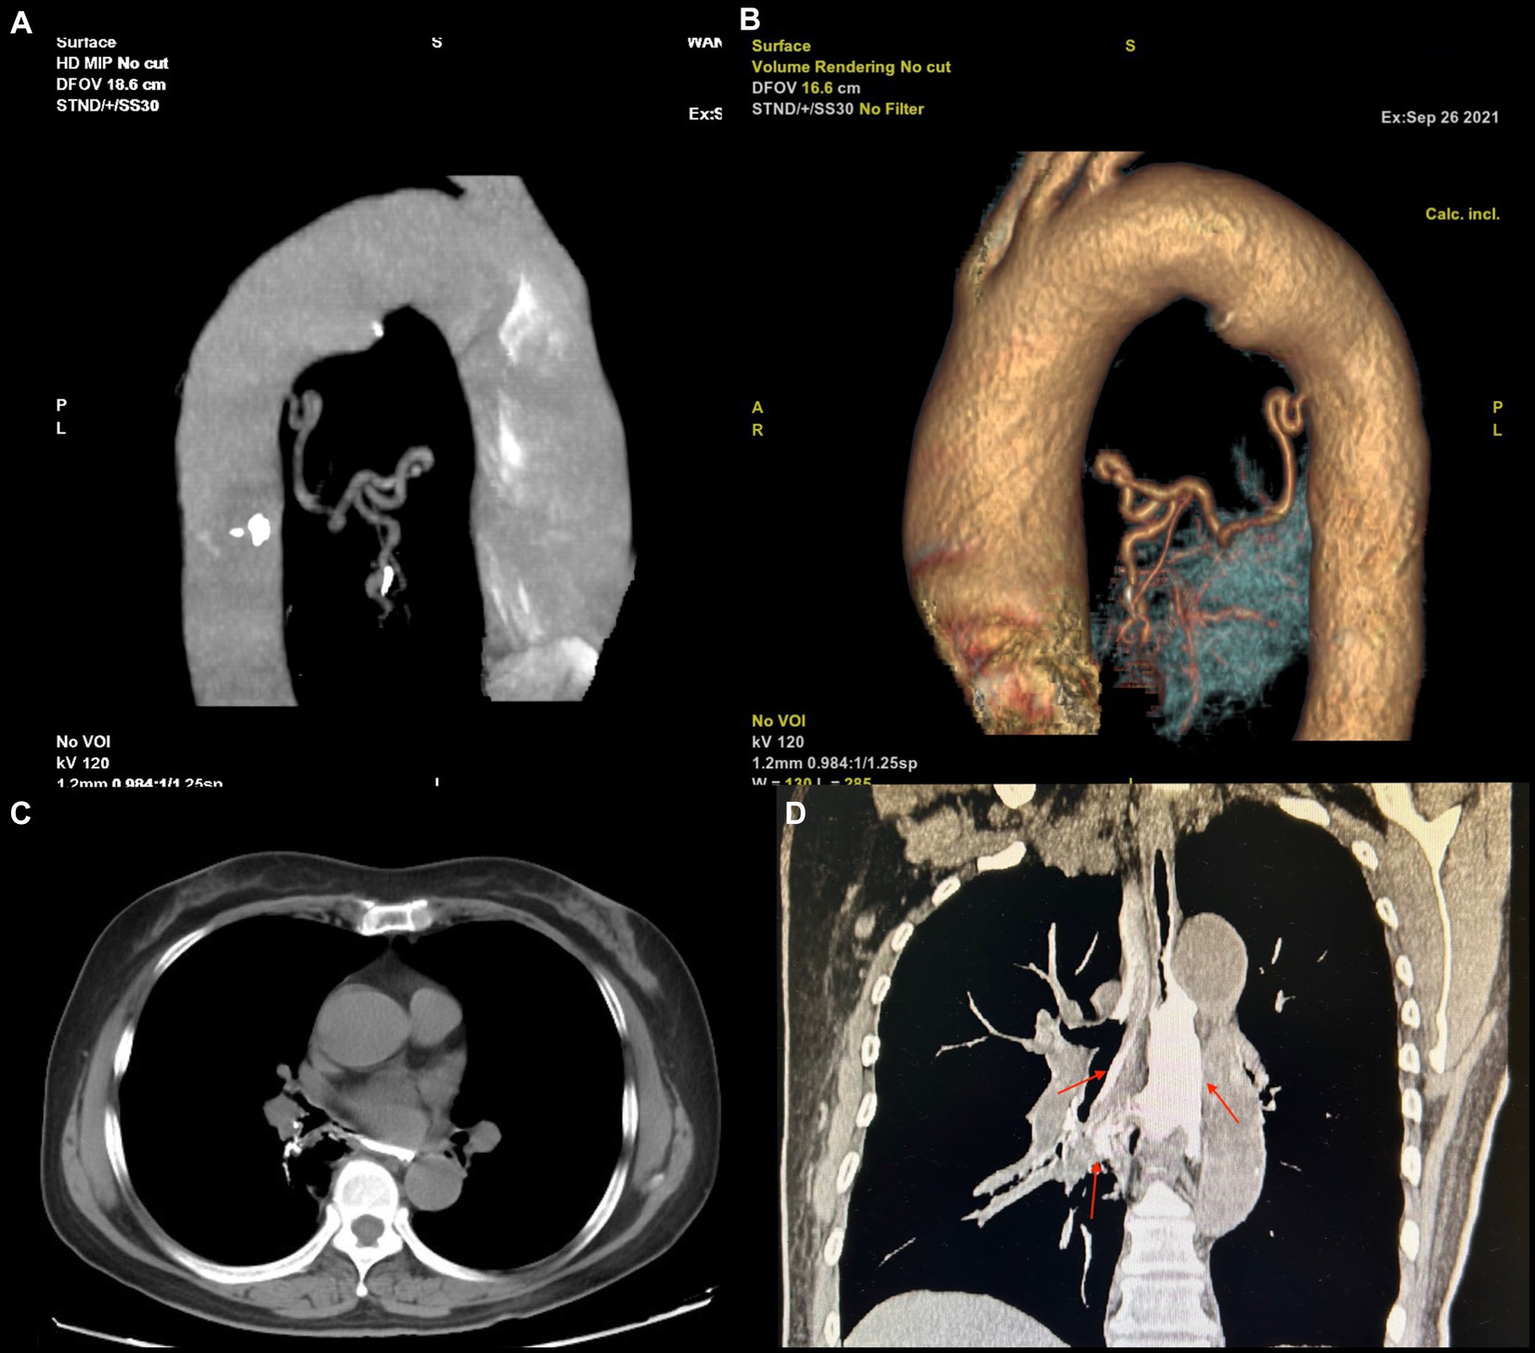

Although the bleeding stopped temporarily after hemostasis treatment, the patient had another episode of massive hemoptysis around 8 h later, expectorating a volume of approximately 700 mL. She subsequently developed confusion, respiratory failure, and hemorrhagic shock. We immediately arranged for a blood transfusion and mechanical ventilation and performed an emergency vascular intervention. Body arterial angiography revealed a twisted and deformed artery originating from the thoracic aorta that was supplying blood to the lesion in the right lower lobe of the lung (Figures 3A,B).

Figure 3

(A,B) The blood supply vascular reconstruction of the lesion reveals a large, tortuous, and malformed artery originating from the descending aorta, extending toward the site of the lesion. (C,D) The upper gastrointestinal (UGI) contrast study. (A) In the axial view, an abnormal communication between the trachea and esophagus is observed. (B) In the coronal view, the contrast agent is seen entering the bronchus through the fistula and remaining within the airway (indicated by a red arrow).

Therefore, arterial embolization of this blood vessel was performed. After polyvinyl alcohol particle embolization (particle size: 350–560 μm), the hemoptysis stopped abruptly. The patient recovered soon after basic treatment and the ventilator was removed. In addition, upper gastrointestinal (UGI) radiography revealed an abnormal connection between the bronchus and esophagus (Figures 3C,D), so we diagnosed the patient with BPFM.